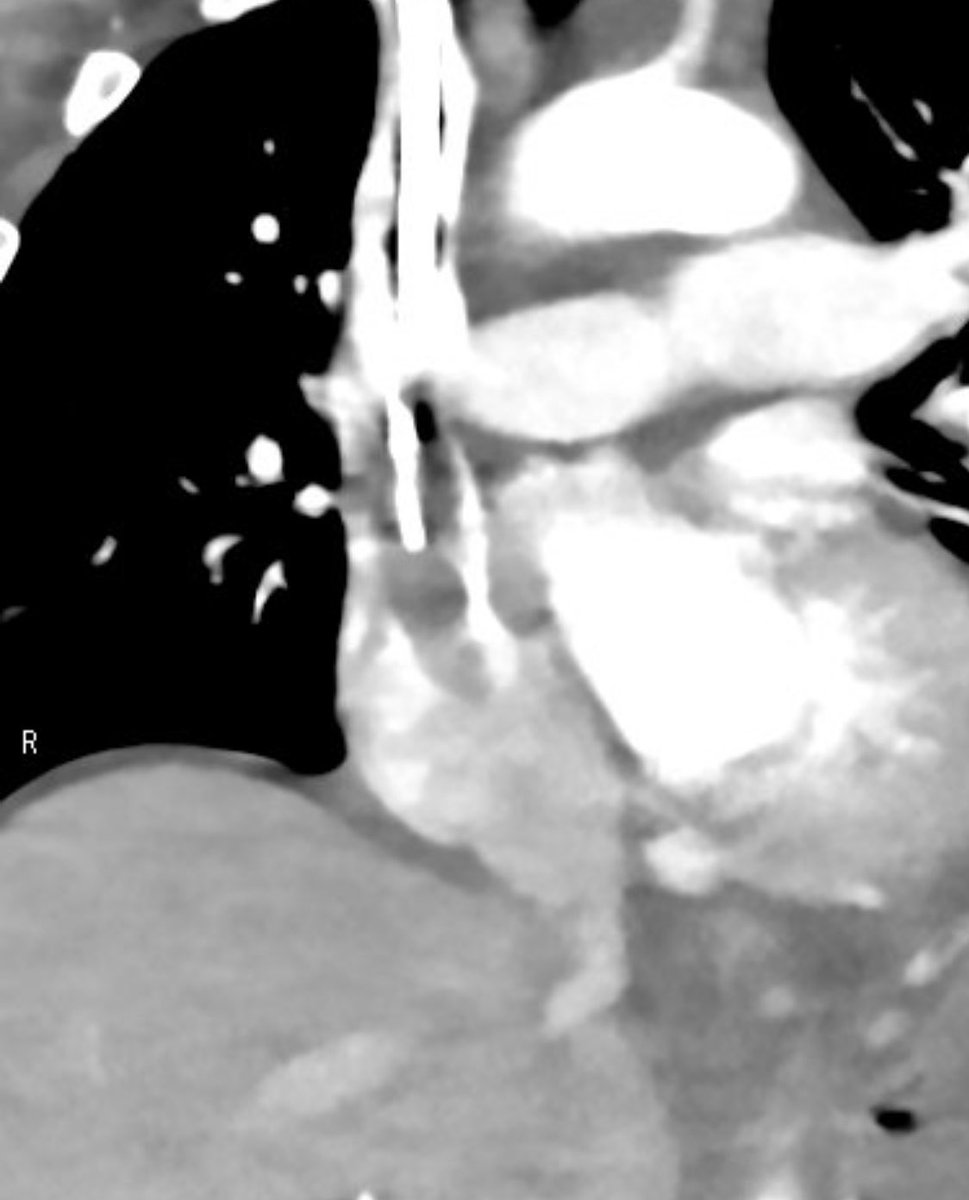

Case 75: with @BhaveshPopat7 . Intranodal Lymphangio(INL)+Thoracic Duct Embo(TDE): coil+glue for chylous pericardium sec to ALL . #irad #medtwitter #cardiotwitter @SriniTummala @TheRealDoctorOs @keithppereira @FadiSaab17 @t_intheleadcoat @SRajesh_IR @IR_Juniors @iRadBIR_Chennai